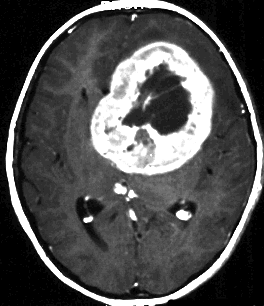

放射線治療がほとんど効かなかった例(高悪性度グリオーマに類似するもの)

手術で簡単にとれそうなPNETです。実際に全摘出していただいて,すぐに脳脊髄照射と腫瘍床照射54グレイの放射線治療を受けたのですが,放射線治療最中に手術摘出した場所から再発してしまいました。再手術で摘出して,シスプラチンを基剤とした併用化学療法やテモゾロマイドを使いましたが,間もなく激しい脳脊髄播種を生じました。MIB-1は70%で,膠芽腫のように強いanaplastyがありました。

放射線治療が最も強力な治療手段なのですが,全く無効なPNETがあります。